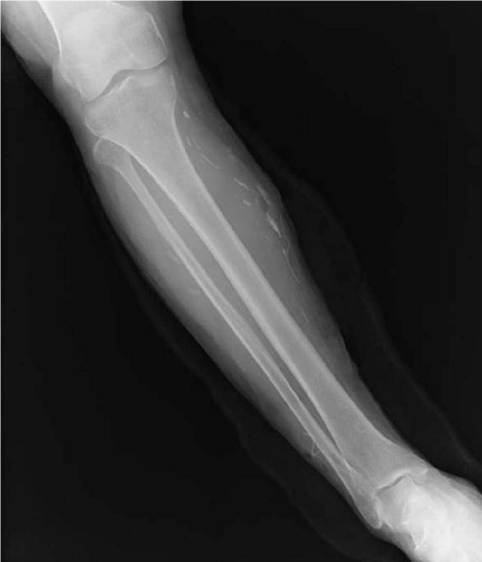

A 60-year-old woman living in Cheonan-si, Chungcheongnam-do, Korea, was admitted to Dankook University Hospital due to pain of the right ankle, aggravated on dorsiflexion. She had noticed a nodular mass at the medial side of the right knee 20 years ago, moving up and down very slowly. She went without any medical care for the lesion, and the mass was not notified for a long time. Three months ago, the mass was found again at the ankle of the patient, developing her ankle pain. On physical examination, an oval, rubber-like mass was found at just proximal to the lateral malleolus of the right foot. The mass was soft, non-tender, and 3 cm in diameter. In addition, another mass was found at the anterior part of the right ankle, and this produced discomfort on dorsiflexion. Routine laboratory tests were unremarkable and no eosinophilia was noted. The plain radiograph of the right leg revealed multiple calcifications extending from the medial part of the knee to the calf (Fig. 1), but nothing was found around the ankle joint. On the MR imaging, heterogeneous signals were observed in the mass, especially near the lateral malleolus (Fig. 2). Epidermoid cyst or dermatomyositis was suspected, and an operation was done on the mass.